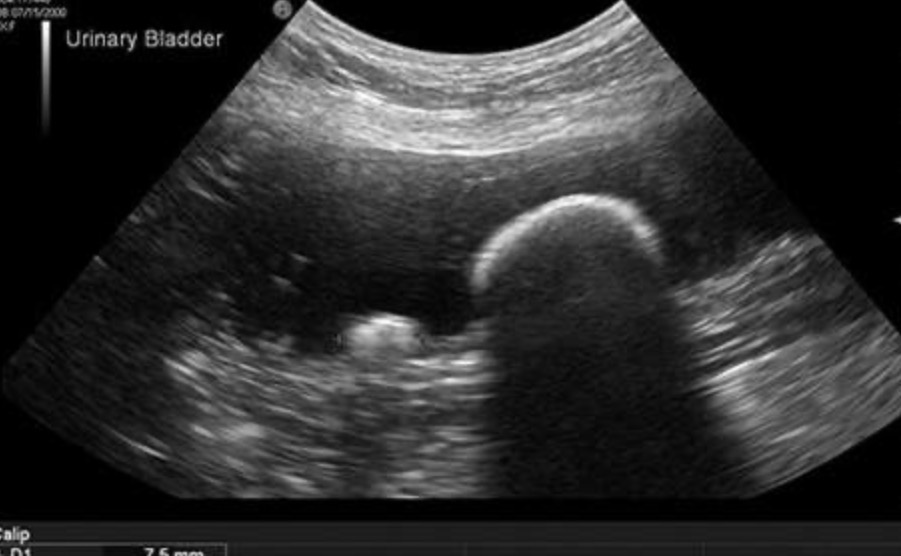

What is the term used to describe the following artefact on this longitudinal scan of the urinary bladder?

Distal acoustic shadowing